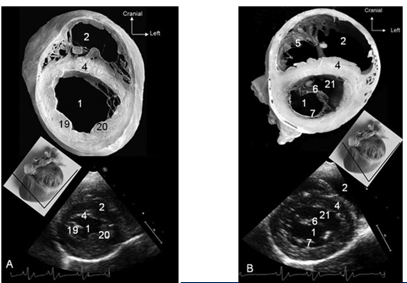

What does this show?

LA size

LV dimensions